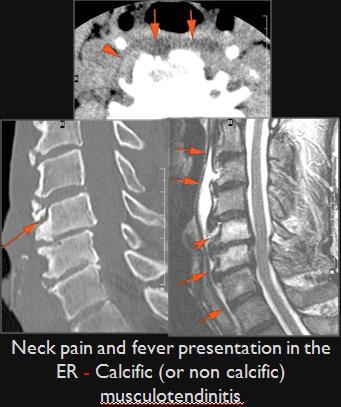

Prevertebral and Epidural Spaces

There is edema/abscess within in the prevertebral or paravertebral spaces.

There is erosive process involving the disc spaces or other components of the spine.